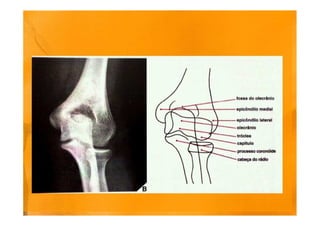

Ressonância magnética do cotovelo direito

Corte coronal, sequência T1 (a)

(a) Osteófitos marginais no côndilo umeral medial e na ulna (setas), irregularidade dos

contornos do osso subcondral do úmero, rádio e ulna

Cortes coronais (anterior para posterior), sequência STIR (b, c)

(b) Indefinição da porção proximal do ligamento colateral radial (seta preta).

Fratura da margem medial da cabeça do rádio, com extensão articular (seta branca).

c) Espessamento heterogêneo e ondulação do tendão comum dos extensores (seta).

Significativo edema dos planos gordurosos da região lateral do cotovelo.

Edema intra-muscular peri-articular

Corte sagital, sequência STIR (f)

Corpo livre intra-articular (seta).

Derrame articular